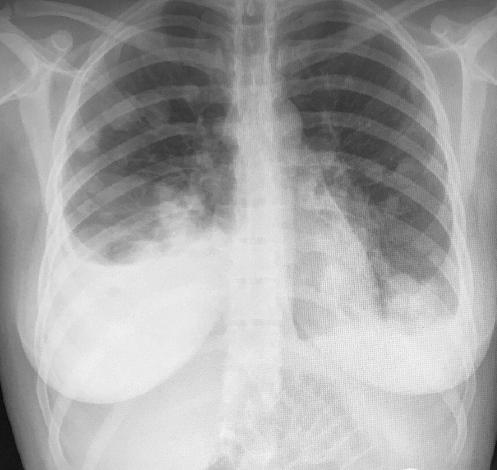

La analítica de sangre muestra una hemoglobina de 9.5 g/dl, b-hCG de 267,789 mUI/ml y hormonas tiroideas elevadas con disminución de la hormona estimulante del tiroides; el resto de los parámetros dentro de la normalidad. La radiografía de tórax se informa con abundantes infiltrados compatibles con metástasis más derrame pulmonar de predominio derecho (Fig. 1). Ante los hallazgos se solicita tomografía computarizada, en la que se objetivan abundantes nódulos en ambos pulmones con componente necrótico (Fig. 2) y placenta posterior con captación heterogénea y crecimientos nodulares/mamelonados (Fig. 3), todo ello compatible con metástasis de coriocarcinoma a confirmar por anatomía patológica.

Figura 1 Radiografía de tórax que muestra infiltrados pulmonares bilaterales compatibles con metástasis con derrame pulmonar de predominio derecho.